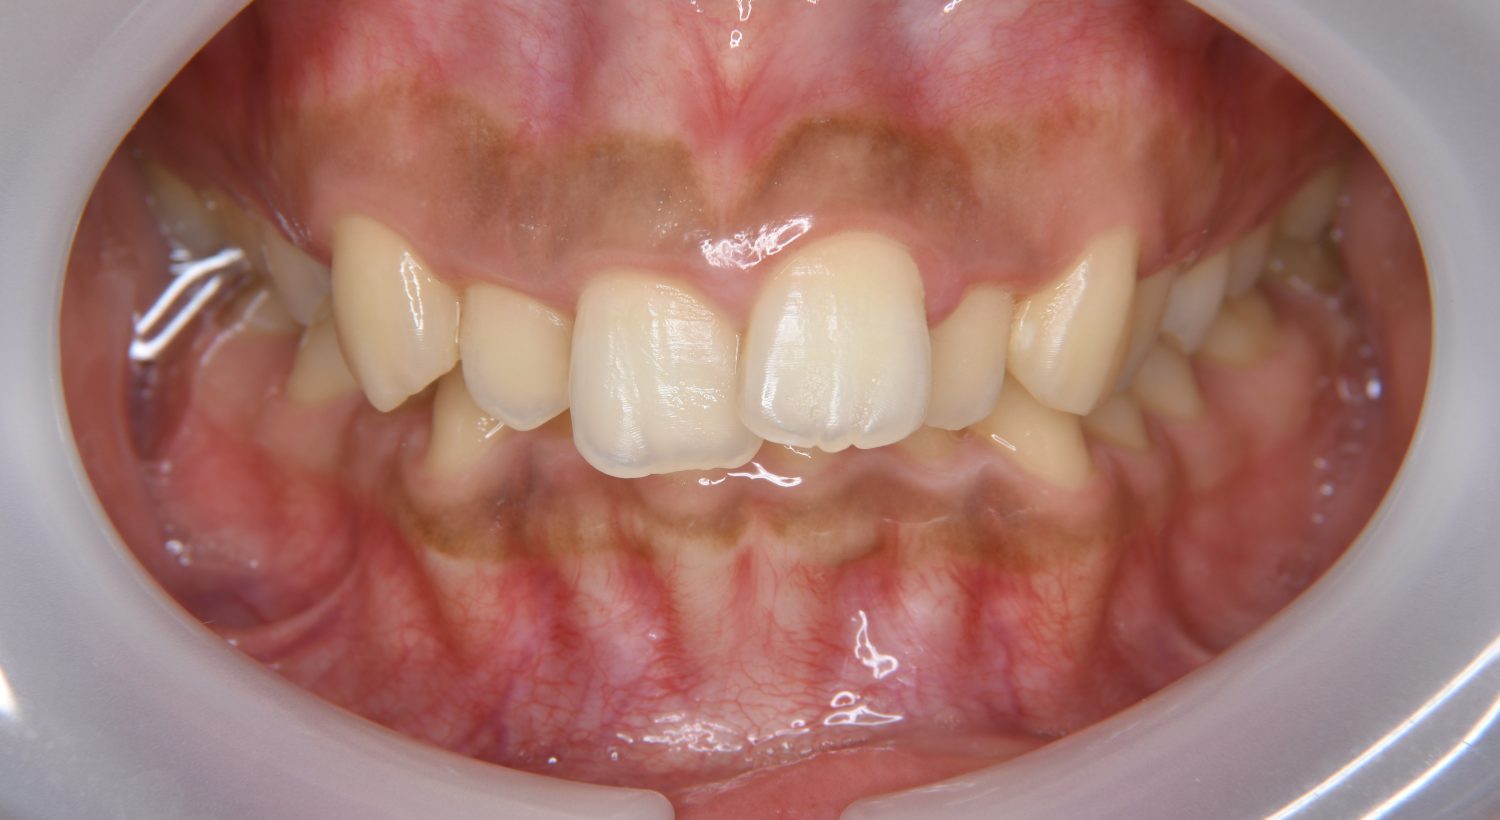

叢生の症例紹介②

Before

主訴

歯の凸凹を治したい。

治療内容

アライナー(インビザライン)にて非抜歯で治療を行いました。

上下前歯部に叢生(凸凹)が認められる状態でした。歯列の遠心移動を行うことで機能面および審美面が改善されました。